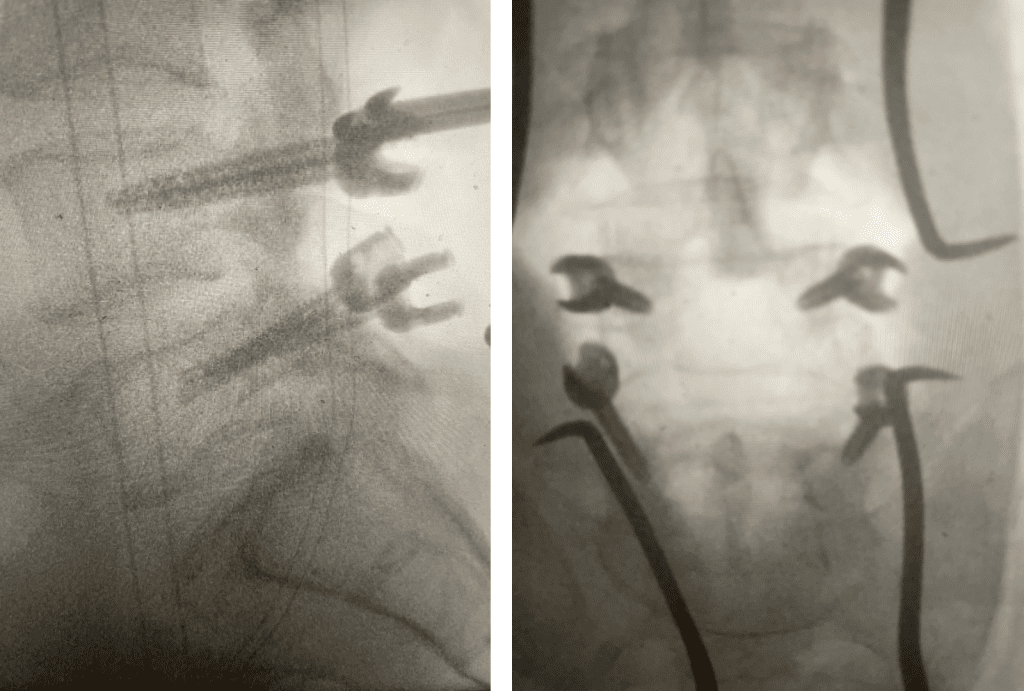

Fig 1: Sagittal and axial T2-weighted lumbar MRI demonstrating severe L4-5 Stenosis and grade 1 spondylolisthesis. Note (yellow arrow) cystic anteromedial extension off the right facet joint causing right-sided lateral recess cut-off of thecal sac and compression of the right L5 nerve root.

This 70 year-old male with two years of right leg pain with minimal low back pain. The patient had tried physical therapy and epidural injections. Neurologically he was intact. MRI revealed a grade 1 spondylolisthesis (slipped spine in Greek) at L4-5 with severe lumbar stenosis mainly due to thickened yellow ligament and overgrown joints; but the thing that I believe put him over the edge was a small joint cyst on the right (Fig 1). People just form cysts. You can get a cyst in practically every organ including kidney, liver, ovarian, etc. People are actually fascinated by them. When patients have spine surgery the only thing that matters to them is, “did you get the cyst?” The fact is that they are these small gelatinous balls that come off the joint space and grow into the spinal canal and cause symptoms by compressing the nerve. You essentially bite them away with our instruments. You really can’t aspirate them through the skin. They are just a form of arthritis and are always benign.